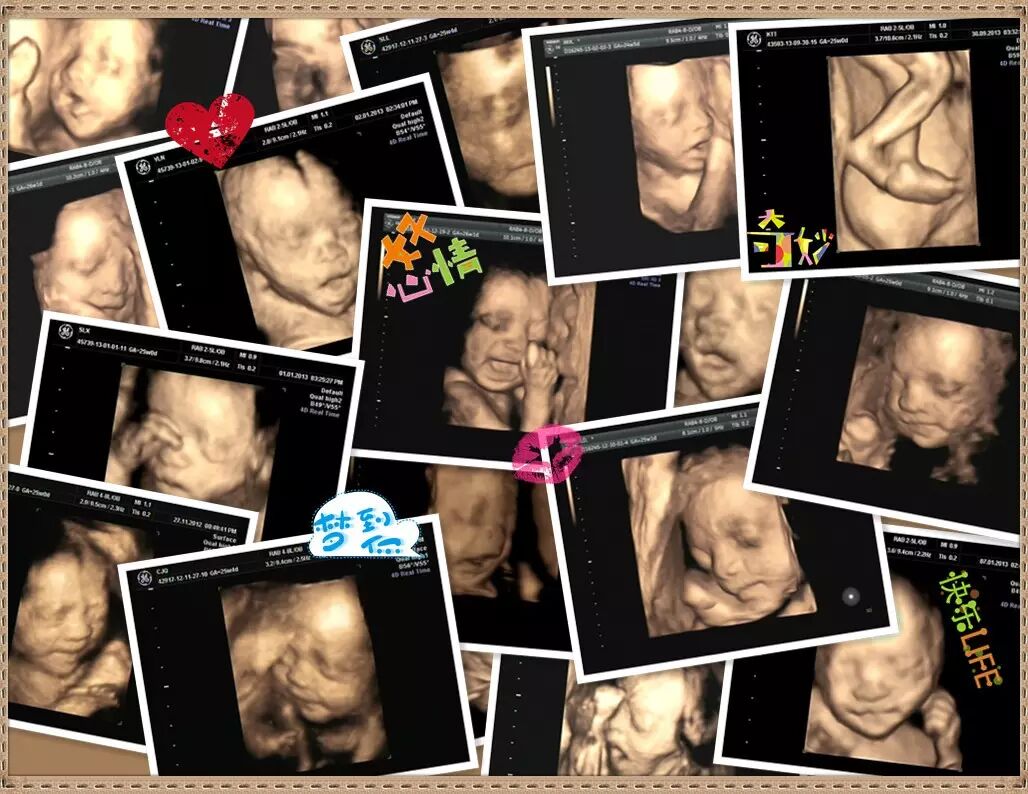

亲爱的孕妈和准爸们,你们还记得第一次看到立体的宝宝模样时的心情吗?难以想象,那张小小的四维彩超图片上出现的小家伙,会是自己此生最难以放下的牵挂。

四维彩超简称“4D”,是目前世界上最为先进的超声诊断技术,能全方位、多角度地观察宫内胎儿生长发育情况,为早期诊断胎儿先天性体表畸形和发育异常提供准确的科学依据。

四维彩超还能清晰显示胎儿在宫内的动态,让准爸妈一起观看宝宝在宫内各种动作神态,体会生命最初的感动。让宝宝拥有独一无二的0岁相册,留下永久的记忆。